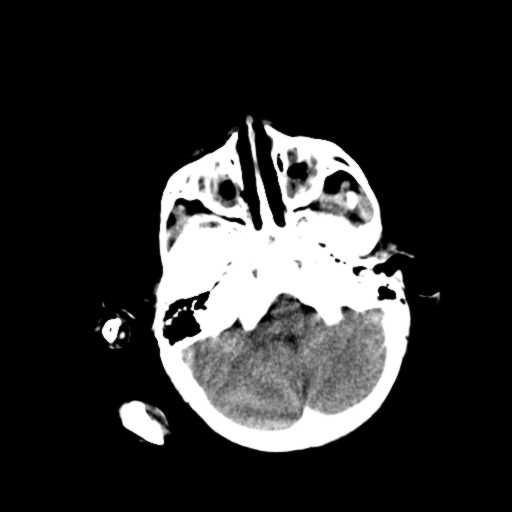

m,3y,外伤一天,无明显其它症状.

有点迷糊了:楼主兄弟要我们做什么?图片没有发全,该继续扫描的没有继续往下扫,不明白。能看的清楚是:

1.双侧上颌窦、筛窦炎。

2.左侧上颌窦后壁部分骨质缺损,内有一牙齿样高密度,周围似乎无明显囊肿形成(没有继续往下扫描,而且只有骨窗,不便观察)。暂考虑左侧上颌窦牙源性囊肿可能。

3.小脑以及右侧颞叶无明显异常,颅盖以及颅底诸骨未见明显骨折,双侧枕骨内板蛛网膜粒压迹多、略深。

1.右小脑半球外侧影为手指产生的伪影?硬膜外血肿?